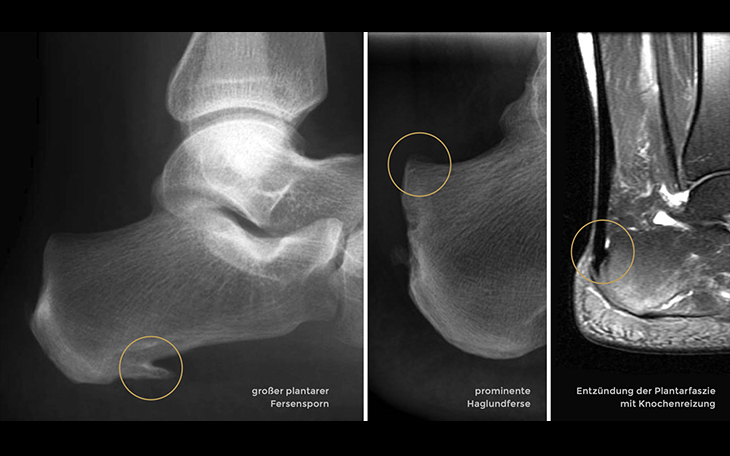

Symptome

Typisch sind stechende Schmerzen im Bereich der Ferse, besonders morgens oder nach längeren Ruhephasen (Anlaufschmerz). Die Schmerzen können sich bei Belastung verstärken und in die Fußsohle ausstrahlen.

Ursachen

Häufige Ursachen sind Überlastung, Fehlbelastung, Übergewicht, falsches Schuhwerk, eine verkürzte Wadenmuskulatur oder ein Knick-Senkfuß.

Konservative Therapie

Dehnübungen der Wadenmuskulatur und der Plantarfaszie, Kühlung, entzündungshemmende Medikamente, Einlagen mit Fersenkissen, Stoßwellentherapie und Injektionen mit Kortikosteroiden oder ACP (Eigenblut) können die Beschwerden lindern.

Operative Therapie

In sehr seltenen Fällen ist eine Operation indiziert. Dabei wird die Plantarfaszie teilweise eingeschnitten oder der Fersensporn abgetragen, um den Druck zu reduzieren und die Entzündung zu beseitigen.